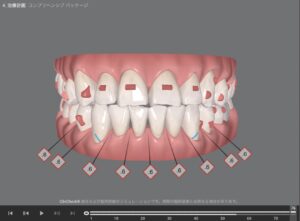

🔶アフター🔶

正面

右

左

治療終了後